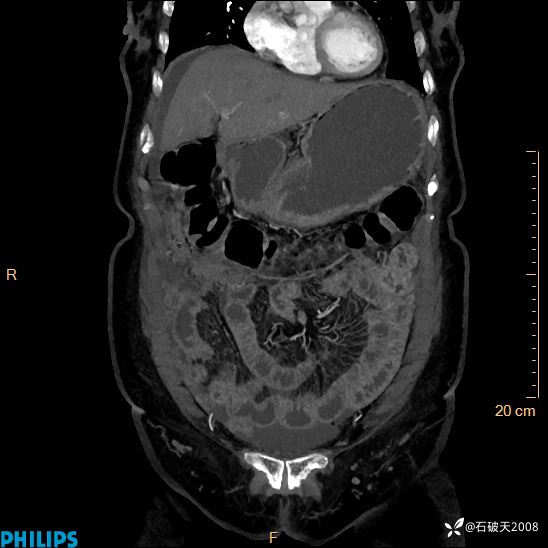

动脉期